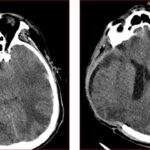

Figura 7. TAC de encéfalo simple (13/01/2023). Marcada concavidad del parénquima cerebral en el sitio de la hemicraniectomía descompresiva compatible con hernia paradójica. Se asocia a borramiento de surcos del hemisferio cerebral derecho con compresión del ventrículo lateral ipsilateral, con desviación de la línea media hacia la izquierda de 7 mm.

En este caso, el paciente desarrolló una hernia paradójica secundaria semanas después de la intervención quirúrgica inicial, manifestándose por colapso del parénquima cerebral bajo el defecto óseo y desviación de la línea media, hallazgos característicos que fueron evidentes en la tomografía cerebral del 13 de enero. La cronología y evolución del cuadro clínico coincide con lo descrito en la literatura, donde este tipo de herniación puede aparecer de forma tardía y empeorar progresivamente si no es reconocida a tiempo.(13, 14)